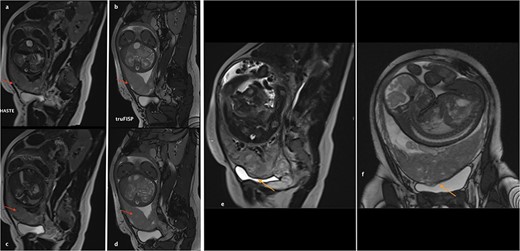

Her MRI showed some thick linear and round bands arising from the maternal side of the placenta seen in low signal in single-shot fast spin echo (SSFSE) T2-Weighted images (HASTE) and in high signal on Balanced Steady State Free Precession (bSSFP) (True Fisp), corresponding to dark intra-placental bands (Fig. 2). The most important finding was myometrial thinning and the bulging of the placenta within the Cesarean scar as well discontinuity in the urinary bladder wall with its invasion by the placental tissue (Fig. 2). These abnormalities were associated to some tortuous bands in a signal on all sequences corresponding to vessels. The diagnosis of placenta percreta was then made and the patient was referred to the obstetrics department for urgent care.

(a)–(d) Sagittal sequences showing dark intra-placental bands (arrows) in low signal in HASTE sequences and in high signal on truFISP. (e) Sagittal HASTE and (f) coronal truFISP sequences showing myometrial thickening and discontinuity in the bladder wall as well as its invasion by the placental tissue (arrow).